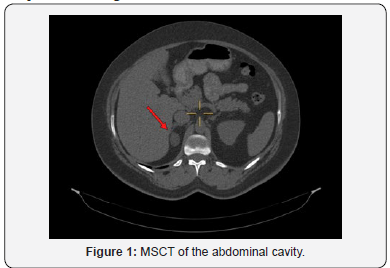

Despite an incomplete examination of the presence and level of hormonal activity of the adrenal gland adenoma, in 2014 the patient was consulted by a surgeon - surgical treatment was not recommended. Subsequently, the frequency of MSCT studies with contrasting was every 1-2 years, the last visualization was carried out in April 2018 (Figures 1 & 2). In the dynamics over 4 years, the size of the formation practically didn’t demonstrate any dynamics. MRI scan of the brain in 2008 revealed no pathology. There are some comorbidities - Autoimmune thyroiditis, diffuse form, goiter 0, Primary subclinical hypothyroidism (takes L-thyroxine 50 μg), thyroid stimulating hormone (November 2017) is 3.8 mIU / ml. There is an atherosclerotic plaque in the right internal carotid artery with minor stenosis (NASCET). The patient has been taking Jess drugs for contraception since 2016. She has two healthy children; she had no operations or fractures.